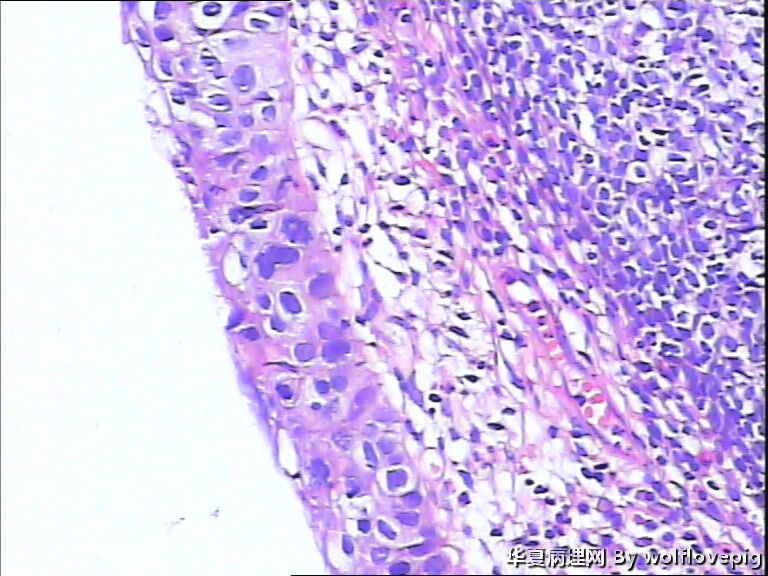

求助,宫颈!

37y

CIN2-3,累腺

CIN3累腺

CIN-II 累及腺体。我看不够原位癌。学习了!

高级别,累腺。

CINIII累及腺体

同意CINIII累及腺体

CINIII 累及腺体